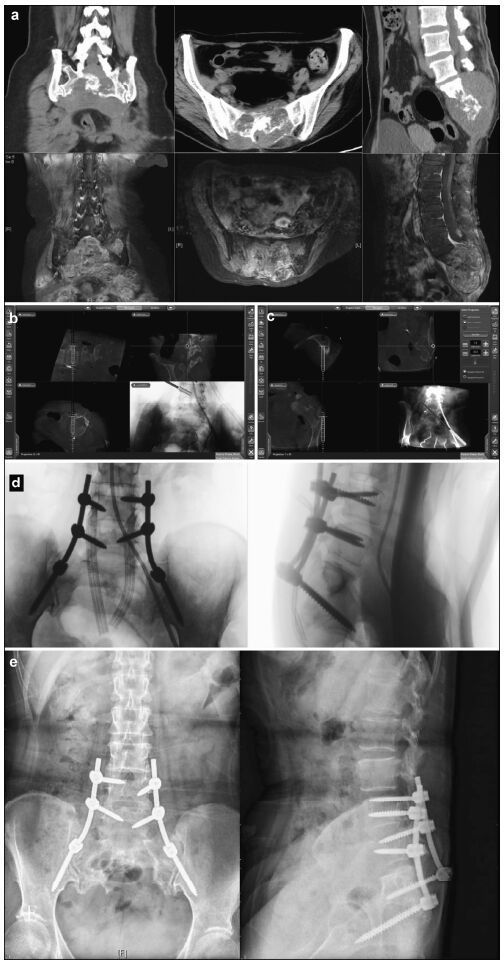

| Figure 4 Preoperative, intraoperative, and postoperative images of patients in the nearly total sacrococcygeal chordoma resection and pedicle screw fixation group. (a) Lumbosacral vertebral computed tomography shows an S1-3 intraspinal isodense tumor and a severely damaged vertebral body. An enhanced magnetic resonance imaging scan shows S1-3 intraspinal internal and external tumors and a vertebral body that has been invaded and damaged. (b) Intraoperative L4 left pedicle screw implantation is performed under navigation. The direction, angle, and depth of the screw entery can be seen to match the navigation plan. (c) Intraoperative right iliac screw implantation is conducted under navigation. The direction, angle, and depth of the screw entering can be seen according to the navigation plan. (d) After screw implantation, an O-arm two-dimensional lateral scan shows good screw positioning. (e) A lateral lumbar radiographic scan, 7 days postoperatively, shows firm pedicle and iliac screw fixation and good positioning. |

| Figure 5 Preoperative, intraoperative, and postoperative images of patients in the percutaneous minimally invasive pedicle internal fixation group. (a) Lumbosacral vertebral computed tomography shows L3 vertebral spondylolisthesis, L3-4 and L4-5 spinal stenosis, intervertebral disc degeneration, and corresponding intervertebral space narrowing. (b) Intraoperative L4 right pedicle screw implantation is performed under navigation. The direction, angle, and depth of screw entry can be seen in real-time, according to the navigation plan. (c, d) Intraoperative screw implantation and bar threading are performed under navigation. (e, f) After screw implantation, O-arm three-dimensional anteroposterior and lateral scans show that the screw is well positioned. |